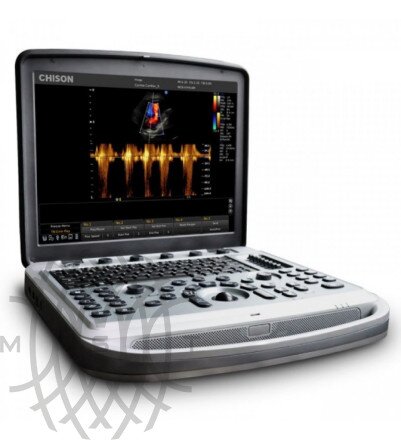

УЗИ аппарат Chison SonoTouch 80 Pro

Характеристики УЗИ аппарат Chison SonoTouch 80 Pro

Переносной ультразвуковой сканер Chison Sonotouch 80 Pro применим для различных сфер - акушерства, гинекологии, урологии, ангиологии, маммологии, кардиологии, ортопедии, педиатрии, неонатологии, ветеринарии, биопсии и т.д. Аппарат выполнен в форме ноутбука с весом до 5.5 кг. Эргономичная панель управления позволяет добраться практически до любой функции за одно нажатие и имеет функцию автоподстройки подсветки в зависимости от окружающего освещения. Sonotouch 80 Pro оснащен бесштырьковым портом для подключения легковесных ультразвуковых датчиков одним движением.

Технические характеристики УЗИ аппарат Chison SonoTouch 80 Pro